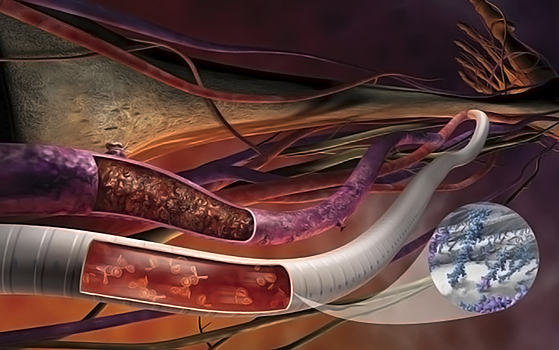

Ученые изготовили синтетическую матрицу из полимолочной кислоты. Это биоразлагаемый полимер, который содержится в организме человека. Оказавшись на нужном месте, матрица растворяется, и на ее месте возникает сосуд. «Сама по себе матрица состоит из нано- и микроволокон, которые очень похожи на волокнистую структуру естественного сосуда. Клетки донора хорошо растут на такой матрице. Мы изучили ее свойства — механическую прочность, пористость, гидрофобность», — отметил сотрудник НИЛ «Полимерные материалы для тканевой инженерии и трансплантологии» СПбПУ Павел Попрядухин.

Чтобы испытать свое изобретение, ученые проводили эксперименты на животных. Они вшивали лабораторным крысам матрицу в брюшную аорту. После этого исследователи наблюдали за животными. Они выяснили, что на промежуточных этапах искусственный сосуд был очень похож на настоящий. А через 16 месяцев после имплантации матрица полностью растворилась. Но в конце исследования ученые обнаружили у крыс расширение сосуда в месте, где они проводили реконструкцию. По словам ученых, чтобы предотвратить развитие таких осложнений, необходимо разработать метод дополнительного укрепления стенки матрицы. Для этого они планируют вставить матрицу в клетки среднего слоя сосуда, который отвечает за прочность.